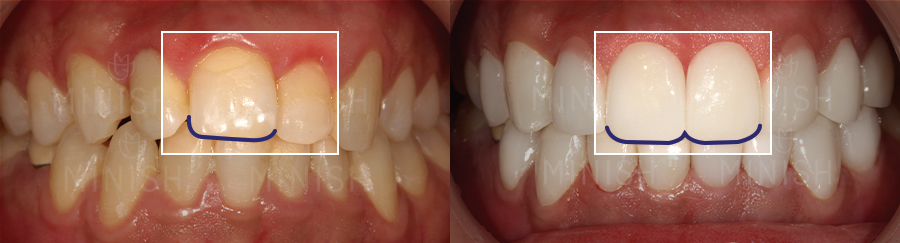

두 번째 앞니(측절치)를 이용한 앞니 복원

● 질환: 선천적 결손치(#21, #35), 치아비대칭, 교합 틀어짐

● 촬영일자: Before 2022.03.16 After 2022.04.08

● 실치료기간: 5일

▼ 가평아들은 앞니 옆의 두 번째 치아(측절치)를 이용하여 결손된 앞니 한 개를 채워주었는데요.

기존 앞니와 잘 어우러질 수 있도록 잇몸 형태와 치아의 크기, 색상까지 여러 측면을 고려해 진행하였습니다. 그 중에서도 치은절제술 및 핑크미니쉬를 통해 잇몸 라인의 대칭을 맞춰주었는데요. 부어있던 잇몸이 빠른 시일 내 건강해질 수 있도록 함은 물론, 자연스러운 잇몸 형태로 개선이 되었습니다. 또한 교합 힘에 의해 잇몸이 내려가 있었던 부분도 핑크미니쉬로 하여금 연분홍빛 잇몸으로 개선되었고, 조화롭고 건강한 잇몸 형태를 띠게 되었습니다.

이OO님의 경우 결손치로 인해 치아들이 쏠리면서 치아비대칭도 심각했는데요. 완벽한 대칭 개선에는 어려움이 있었지만, 미니쉬 솔루션을 통해 앞니를 복원하고 치아비대칭도 자연스럽게 개선이 되었습니다.